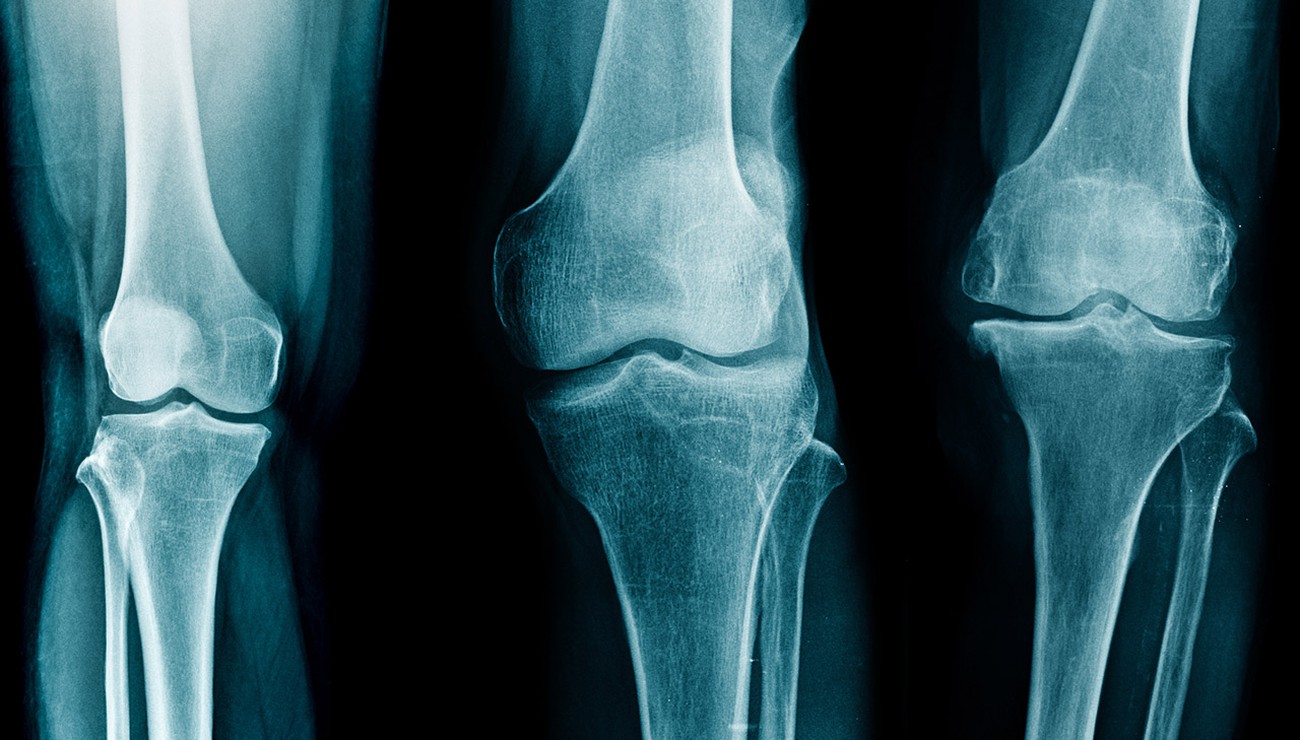

Des chercheurs développent une technique d’imagerie capable de voir les os et les tissus mous à la fois, utile pour détecter l’arthrose en amont, annonçait l’Inserm le 3 janvier passé.

D’ après la même source, les chercheurs travaillent sur une nouvelle technique, appelée « imagerie par contraste de phase aux rayons X ». Cette technique permet de voir les os, d’une part, mais « elle mesure également la déviation des rayons X par les tissus, que l’on appelle “réfraction” ».

« Les tissus mous et cartilagineux dévient 2 000 fois plus ces rayons qu’ils ne les absorbent. Ainsi, ils apparaissent aussi sur les images obtenues », rappelle l’Inserm.

Cette méthode d’imagerie, l’ICP, permettrait d’avoir des images plus claires, plus complètes, avec davantage de détails que les techniques traditionnelles. Elle évite d’avoir besoin de réaliser un IRM, une échographie et une radio sur une même partie du corps pour analyser les tissus denses et les tissus mous.

Les micro-calcifications sont par ailleurs plus visibles. Le système est par contre très onéreux à mettre en place, les chercheurs estiment qu’il pourrait être disponible d’ici 5 ans.